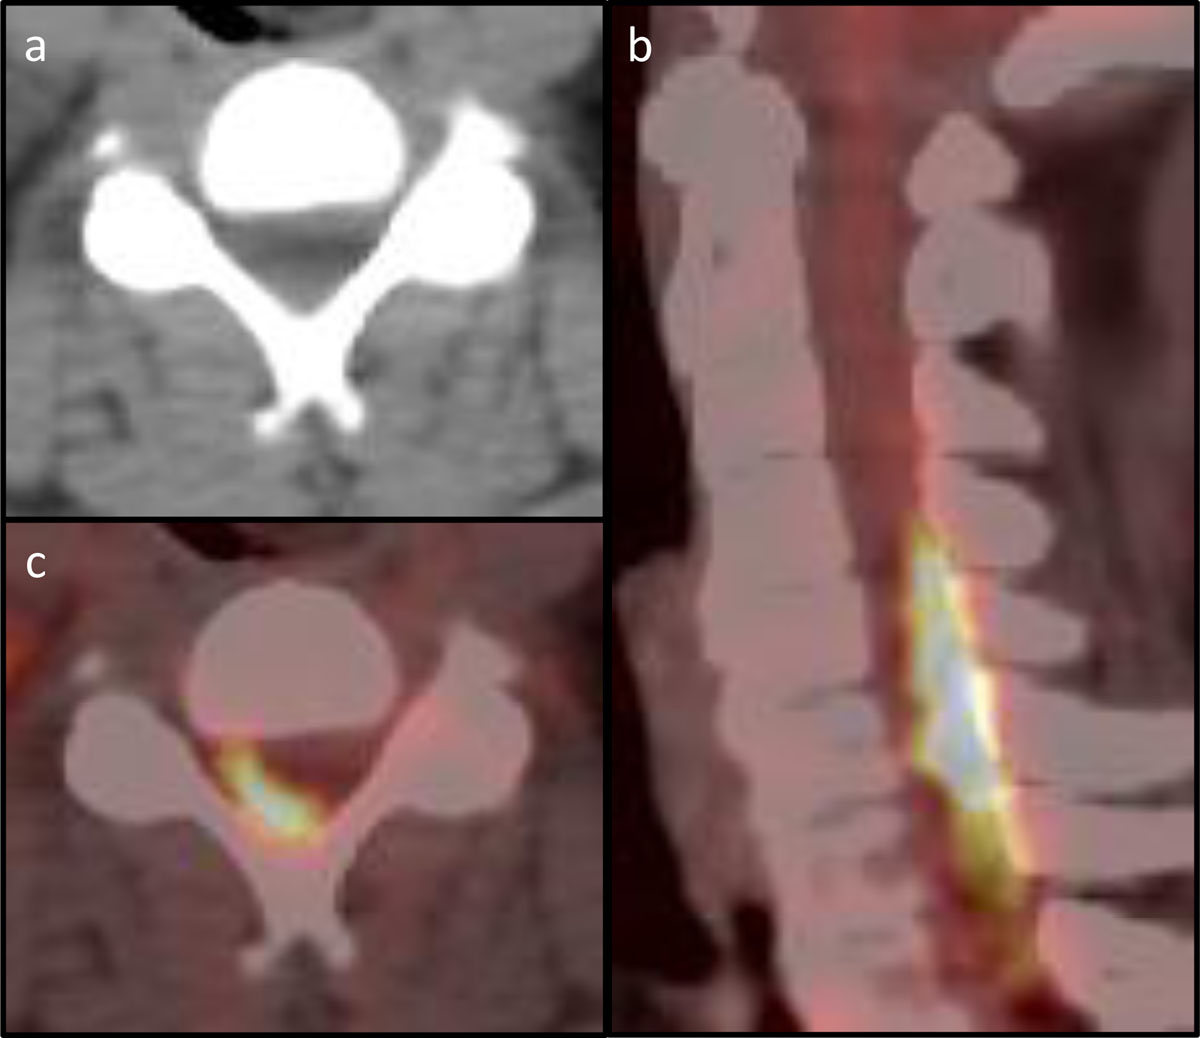

Figure 2

PET-CT of the cervical spine. (a) Axial CT at vertebral level C4 with barely visible posterior epidural mass. (b) Axial PET-CT of vertebral level C4 with notable FDG-avid disease in the spinal canal. (c) Sagittal PET-CT with FDG-avid disease posteriorly within the spinal canal.